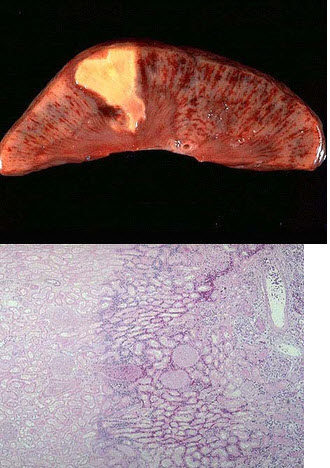

152、单项选择题

脾脏是由终末动脉供血的器官,当某支动脉完全阻塞时会引起相应部位组织的缺血坏死。

如图为病变脾脏肉眼观,该病变应属于()

A.出血性梗死

B.贫血性梗死

C.凝固性坏死

D.液化性坏死

E.灶状坏死